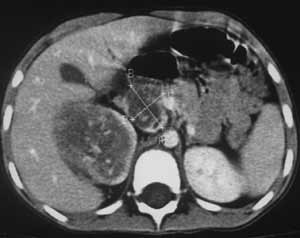

Рис 5. Нефробластома справа у больной 6 лет. Крестом отмечен опухолевый тромб (дефект контрастирования) в просвете НПВ, контрастное вещество визуализируется в просвете сосуда тонкой пристеночной полоской.